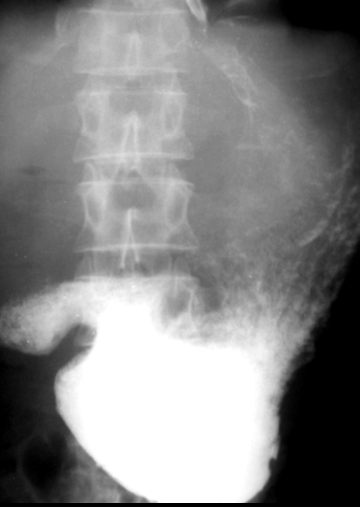

Volvulus gastric